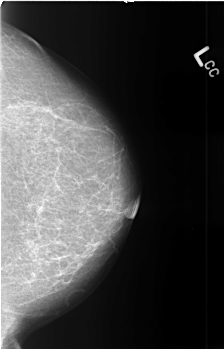

B_3444_1.LEFT_CC

LEFT_CC LINES 4528 PIXELS_PER_LINE 2904 BITS_PER_PIXEL 12 RESOLUTION 50 NON_OVERLAY

RIGHT_CC LINES 4464 PIXELS_PER_LINE 2960 BITS_PER_PIXEL 12 RESOLUTION 50 NON_OVERLAY